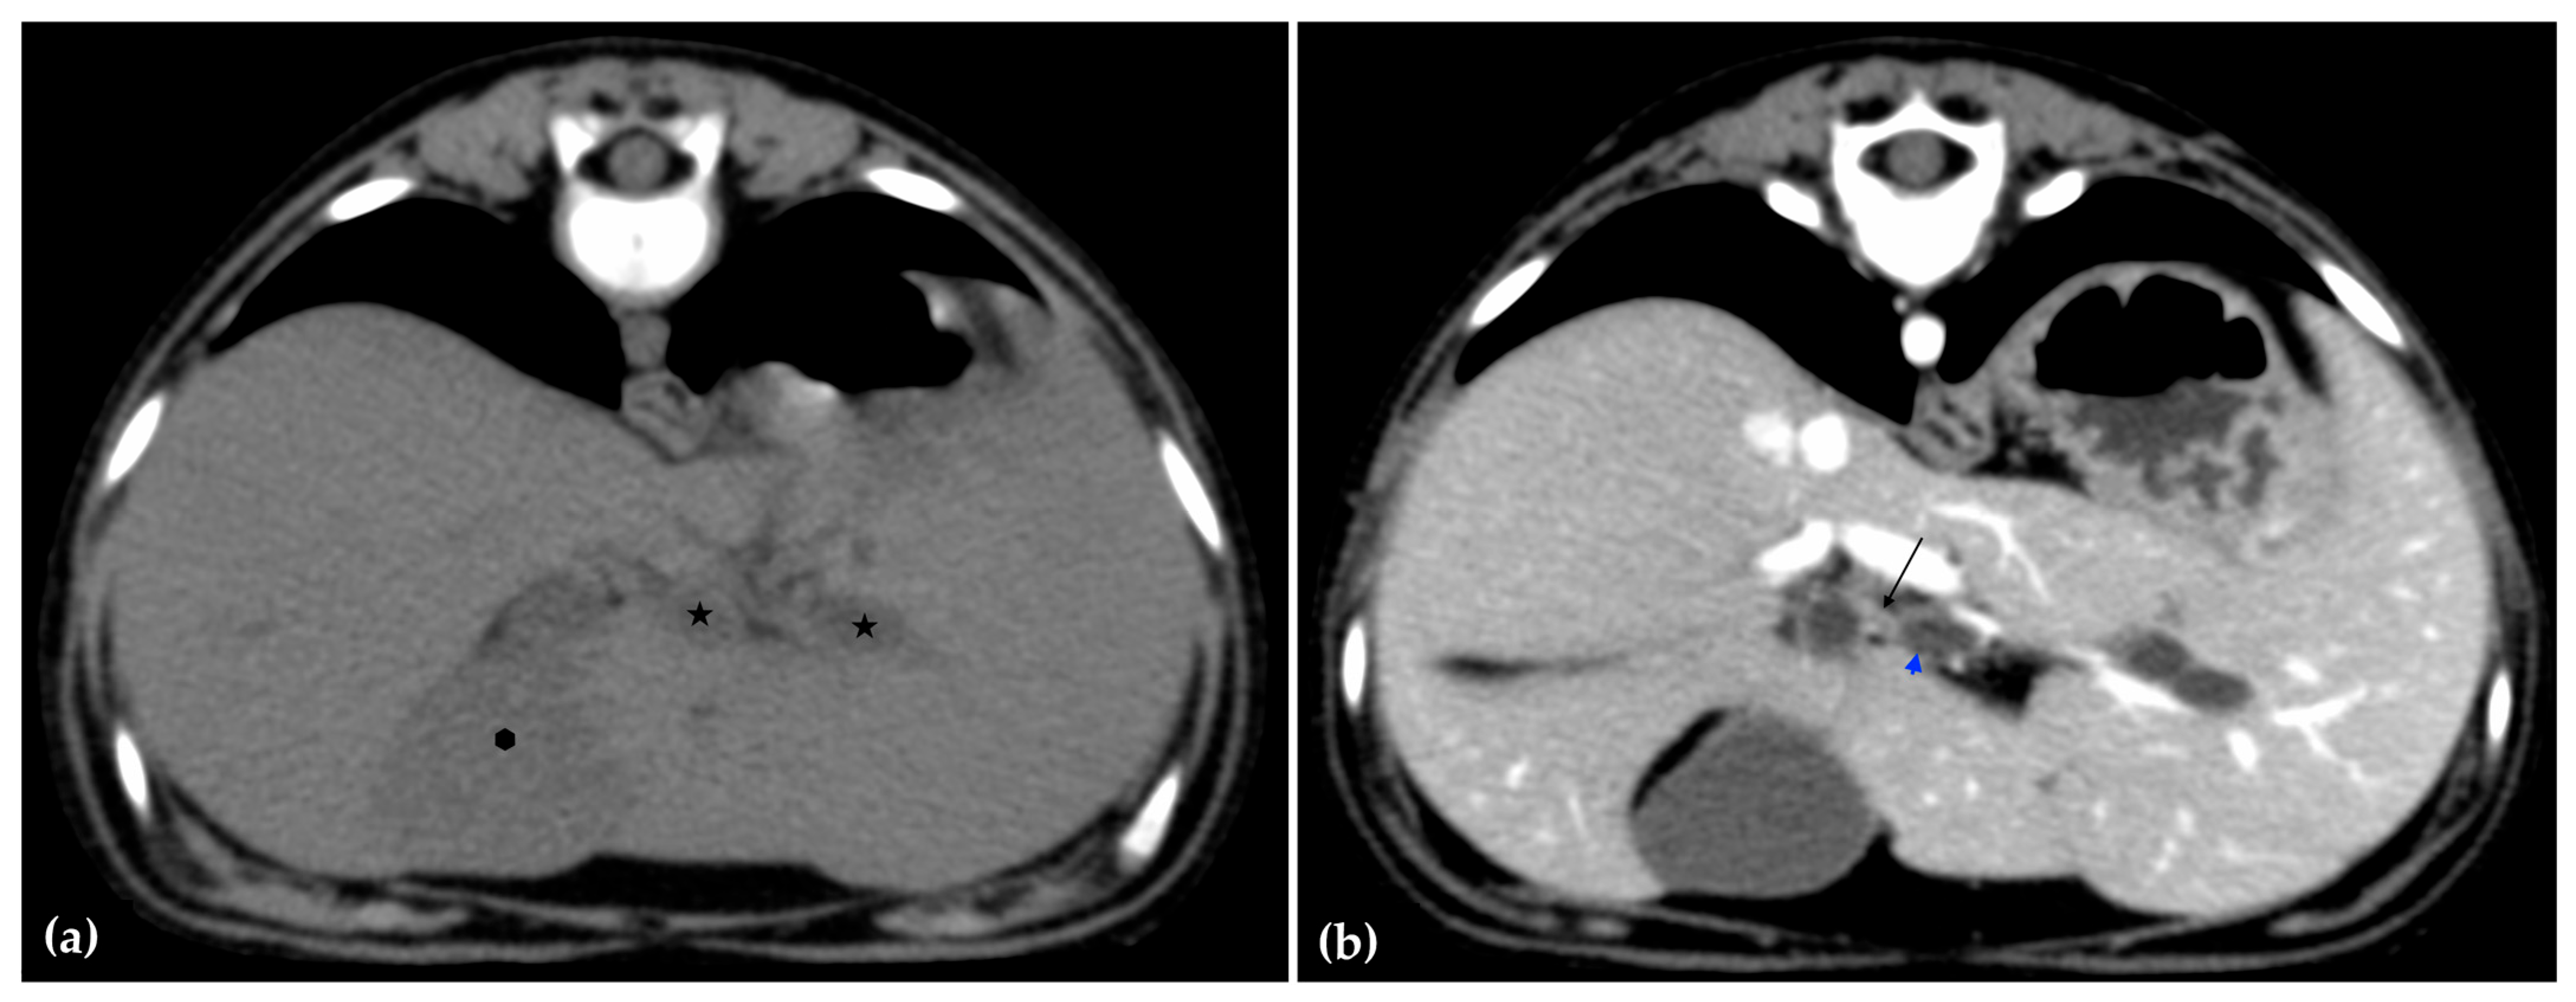

The patient was positioned in sternal recumbency. Helical scans of the abdomen using a multidetector CT were obtained with pre-contrast, post-contrast arterial, portal, and delayed images, all in a soft tissue reconstruction kernel (acquisition parameters: Slice thickness 0.9 mm, pitch 0.8, tube rotation time 0.5 s, 412 mA, 120 kVp, 512 × 512 matrix; Philips Brilliance-40, Philips International B.V., Amsterdam, Netherlands). Prior to contrast administration, the gallbladder was noted to be filled with predominantly mildly hyperattenuating (av. 25 HU) fluid. Dilation of the distal left intrahepatic biliary ducts were again seen (Figure 3a). Following intravenous contrast administration (Optiray 350™ Ioversol, Mallinckrodt Inc., Hazelwood, MO, USA; or Omnipaque 350™ Iohexol, GE Healthcare Inc., Marlborough, MA, USA), multifocal dilation and tortuous narrowing of the CBD was seen and best appreciated in the portal phase. There was increased conspicuity of the walls, both in contrast enhancement and wall thickness (Figure 3b and Figure 4a,b). No intraluminal debris or extraluminal structures to explain the multifocal dilation was appreciated.

Figure 3.

Computed tomographic (CT) pre-contrast image of the liver at the level of the gallbladder (hexagon). There is distention of the left distal intrahepatic biliary ducts (stars). The right of the patient is on the left (a). Computed tomographic (CT) post-contrast image (portal phase) at the level of the cystic duct (black arrow). Immediate dilation of the common bile duct (blue arrowhead) (b).

Figure 4.

Computed tomographic (CT) post-contrast image (portal phase) at the level of the duodenal papilla (arrowhead) and duodenum (star). Focal dilation of the distal common bile duct (CBD, arrow) (a). Computed tomographic (CT) post-contrast image (portal phase) of the tortuous mid common bile duct (arrow) (b).